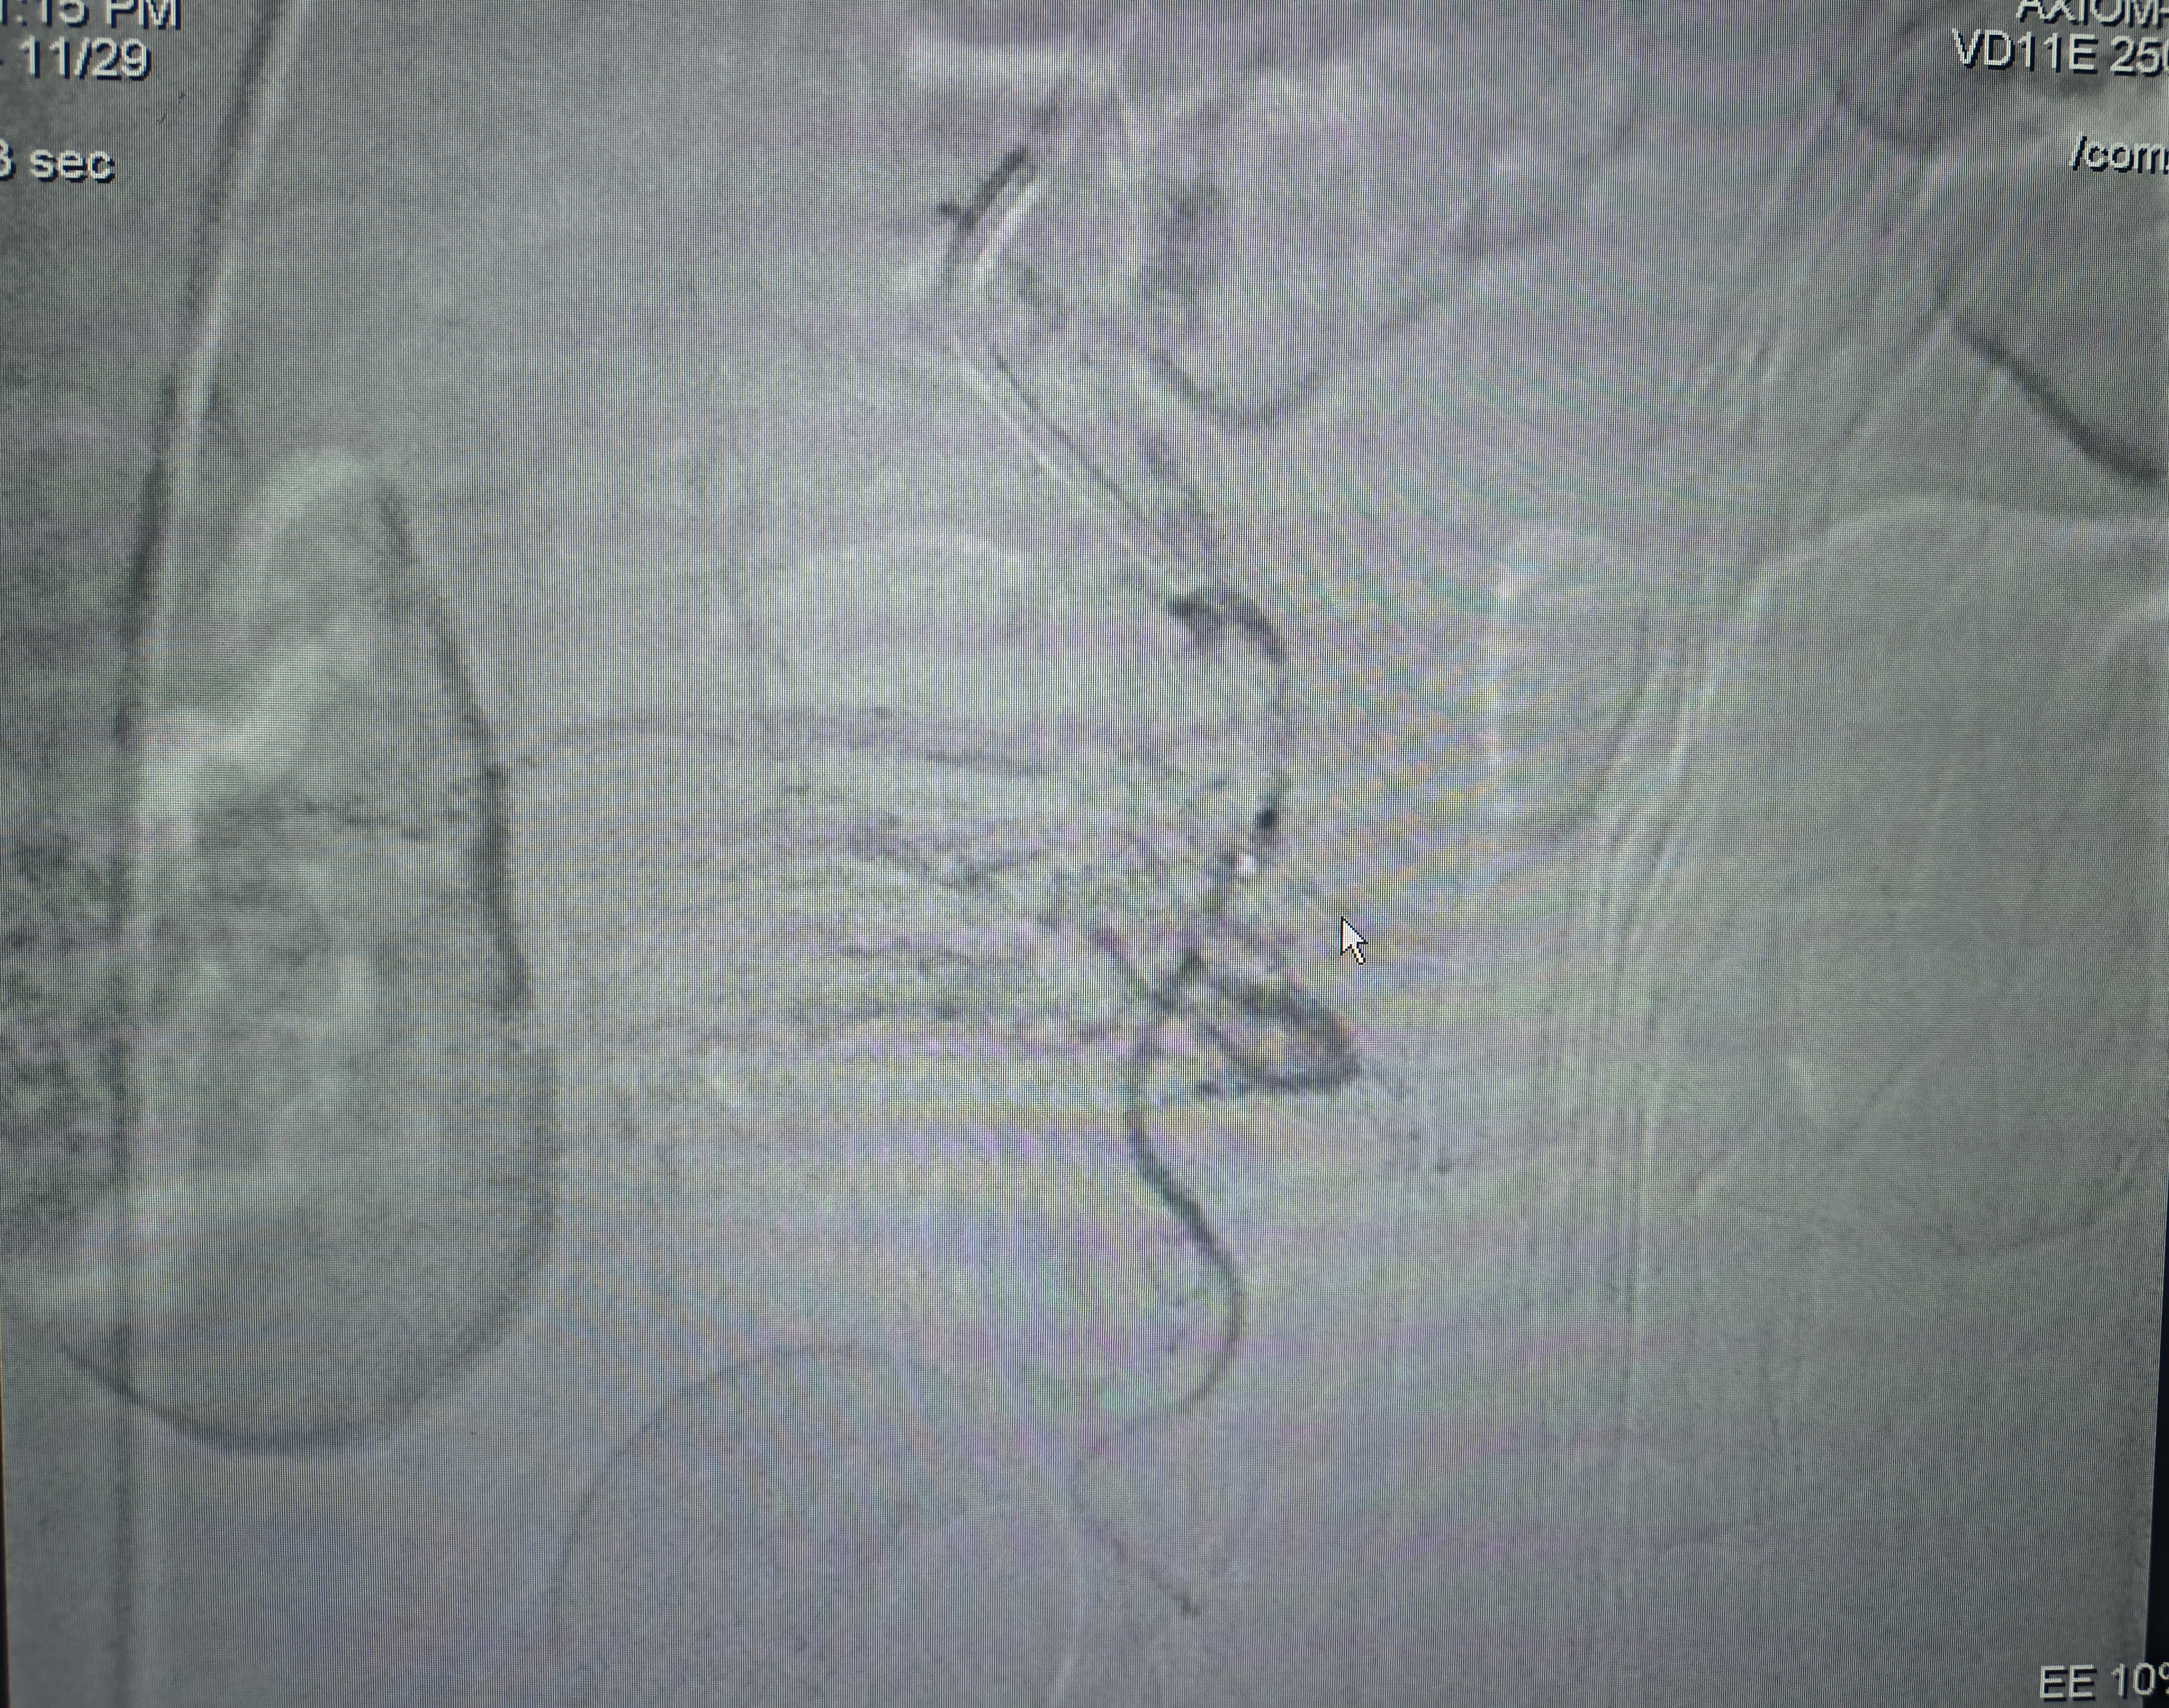

Prostate Artery Embolization